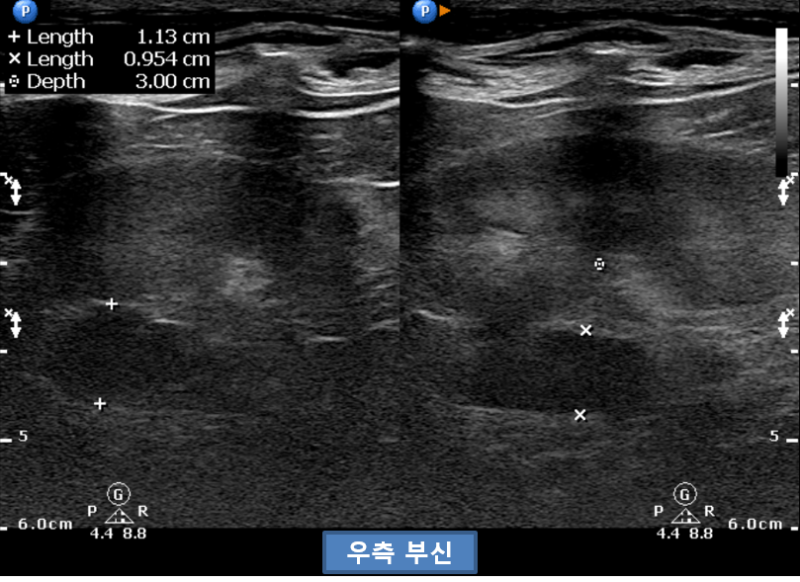

초음파상에서 양측 부신종대(왼쪽 11-12mm, 오른쪽 10-11mm)가 확인되었습니다.